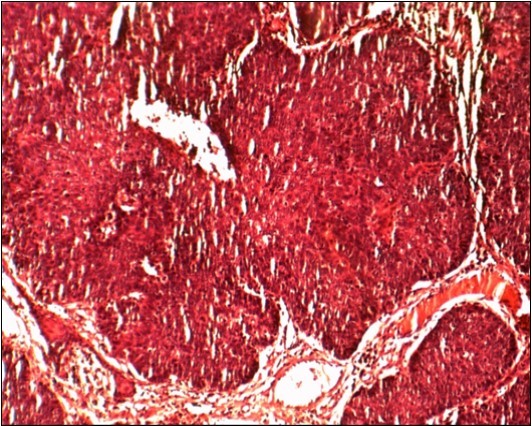

Pathological Findings:

All 23 patients presented invasive differentiated squamous cell carcinoma (Figure 3). None in situ carcinoma was found.

Figure 3.Imature Squamous cell carcinoma ,Hématein Eosin Coloration (HEX100):Epideremoid growth pattern without kératization